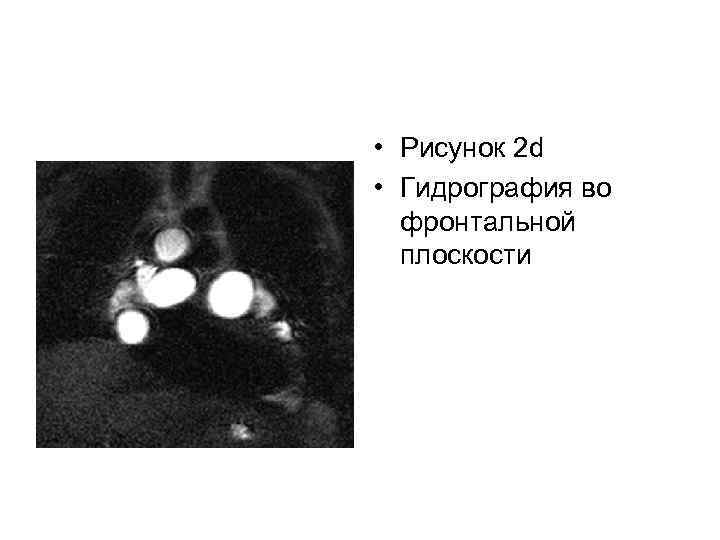

• Рисунок 2 d • Гидрография во фронтальной плоскости